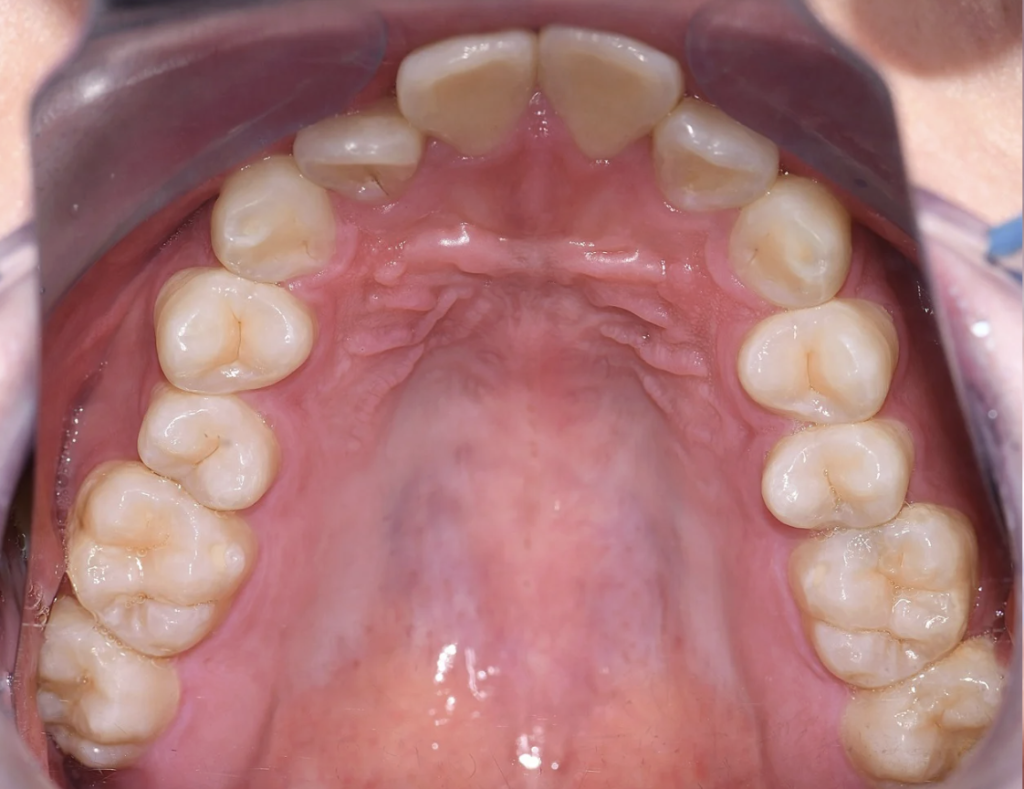

永久歯に大きさに対し、歯を並べるスペース(顎)が小さく、

上下ともに狭窄歯列、下顎前歯には叢生(歯のガタつき)、上顎前歯の突出感が認められました。